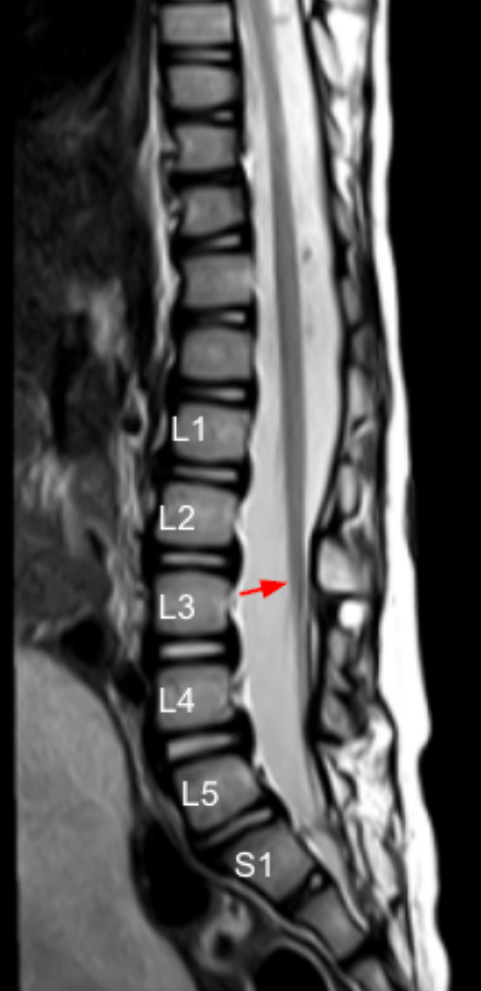

The conus medullaris level refers to the vertebral level at which the spinal cord tapers to form the conus before continuing as the cauda equina. Determining this level is essential for identifying tethered cord syndrome, congenital anomalies, tumors, trauma, or postsurgical complications.

• Identify the spinal cord tapering point where the cord transitions into the cauda equina — this is the conus medullaris tip.

• Count vertebral bodies caudally from T12 to accurately identify the corresponding level.

• Assign the conus termination to the nearest vertebral body or intervertebral disc level (e.g., upper L1, L1–L2 disc, mid-L2).

• Record the level as a specific anatomic location, not just a vertebral number (e.g., “upper L1 body”).

• Normal range: T12-L2

• Low-lying/possible tethered cord: Below L2 vertebral body

• High-riding conus: Above T12 (rare, congenital or post-traumatic)

• Most adults have conus termination at the L1–L2 disc level or upper L2 body.